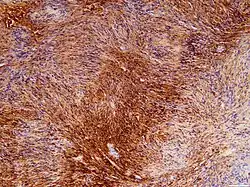

Die Therapie besteht in der chirurgischen Entfernung (Resektion) oder Bestrahlung. Anschließend erfolgt eine histopathologische Untersuchung des Operationspräparates unter dem Lichtmikroskop (Histologie).

- Histologisches Bild eines Schwannoms mit ausführlicher Erklärung